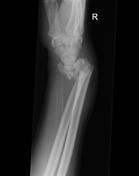

Galeazzi fracture

Usually due to fall on outstretched hand with elbow in flexion